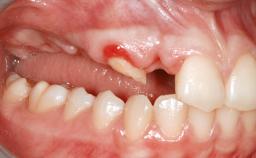

A 20-year-old woman was referred for implant therapy in 2004. Her medical history revealed no significant findings, and neither did she smoke nor take any medications. An extraoral examination revealed no abnormalities of the skin, hair or nails. The intraoral examination revealed only 11 permanent teeth clinically. These were normal in shape, size, and color. In addition, eight retained deciduous teeth (53, 62, 63, 71, 72, 73, 81, 82) were present. No abnormalities were detected during the general examination. The family history revealed that the patient’s father and two sisters were on record with similar conditions. The clinical examination revealed a thick gingival biotype. No recession of the attached gingiva was noted, but the retained deciduous teeth were mobile and unsightly. As a syndrome had not been diagnosed, the case was categorized as non-syndromic oligodontia.

Bone Volume Horizontally and vertically sufficient Horizontally deficient Deficient vertically or deficient vertically AND horizontally

Bone Volume Deficient horizontally, requiring prior grafting